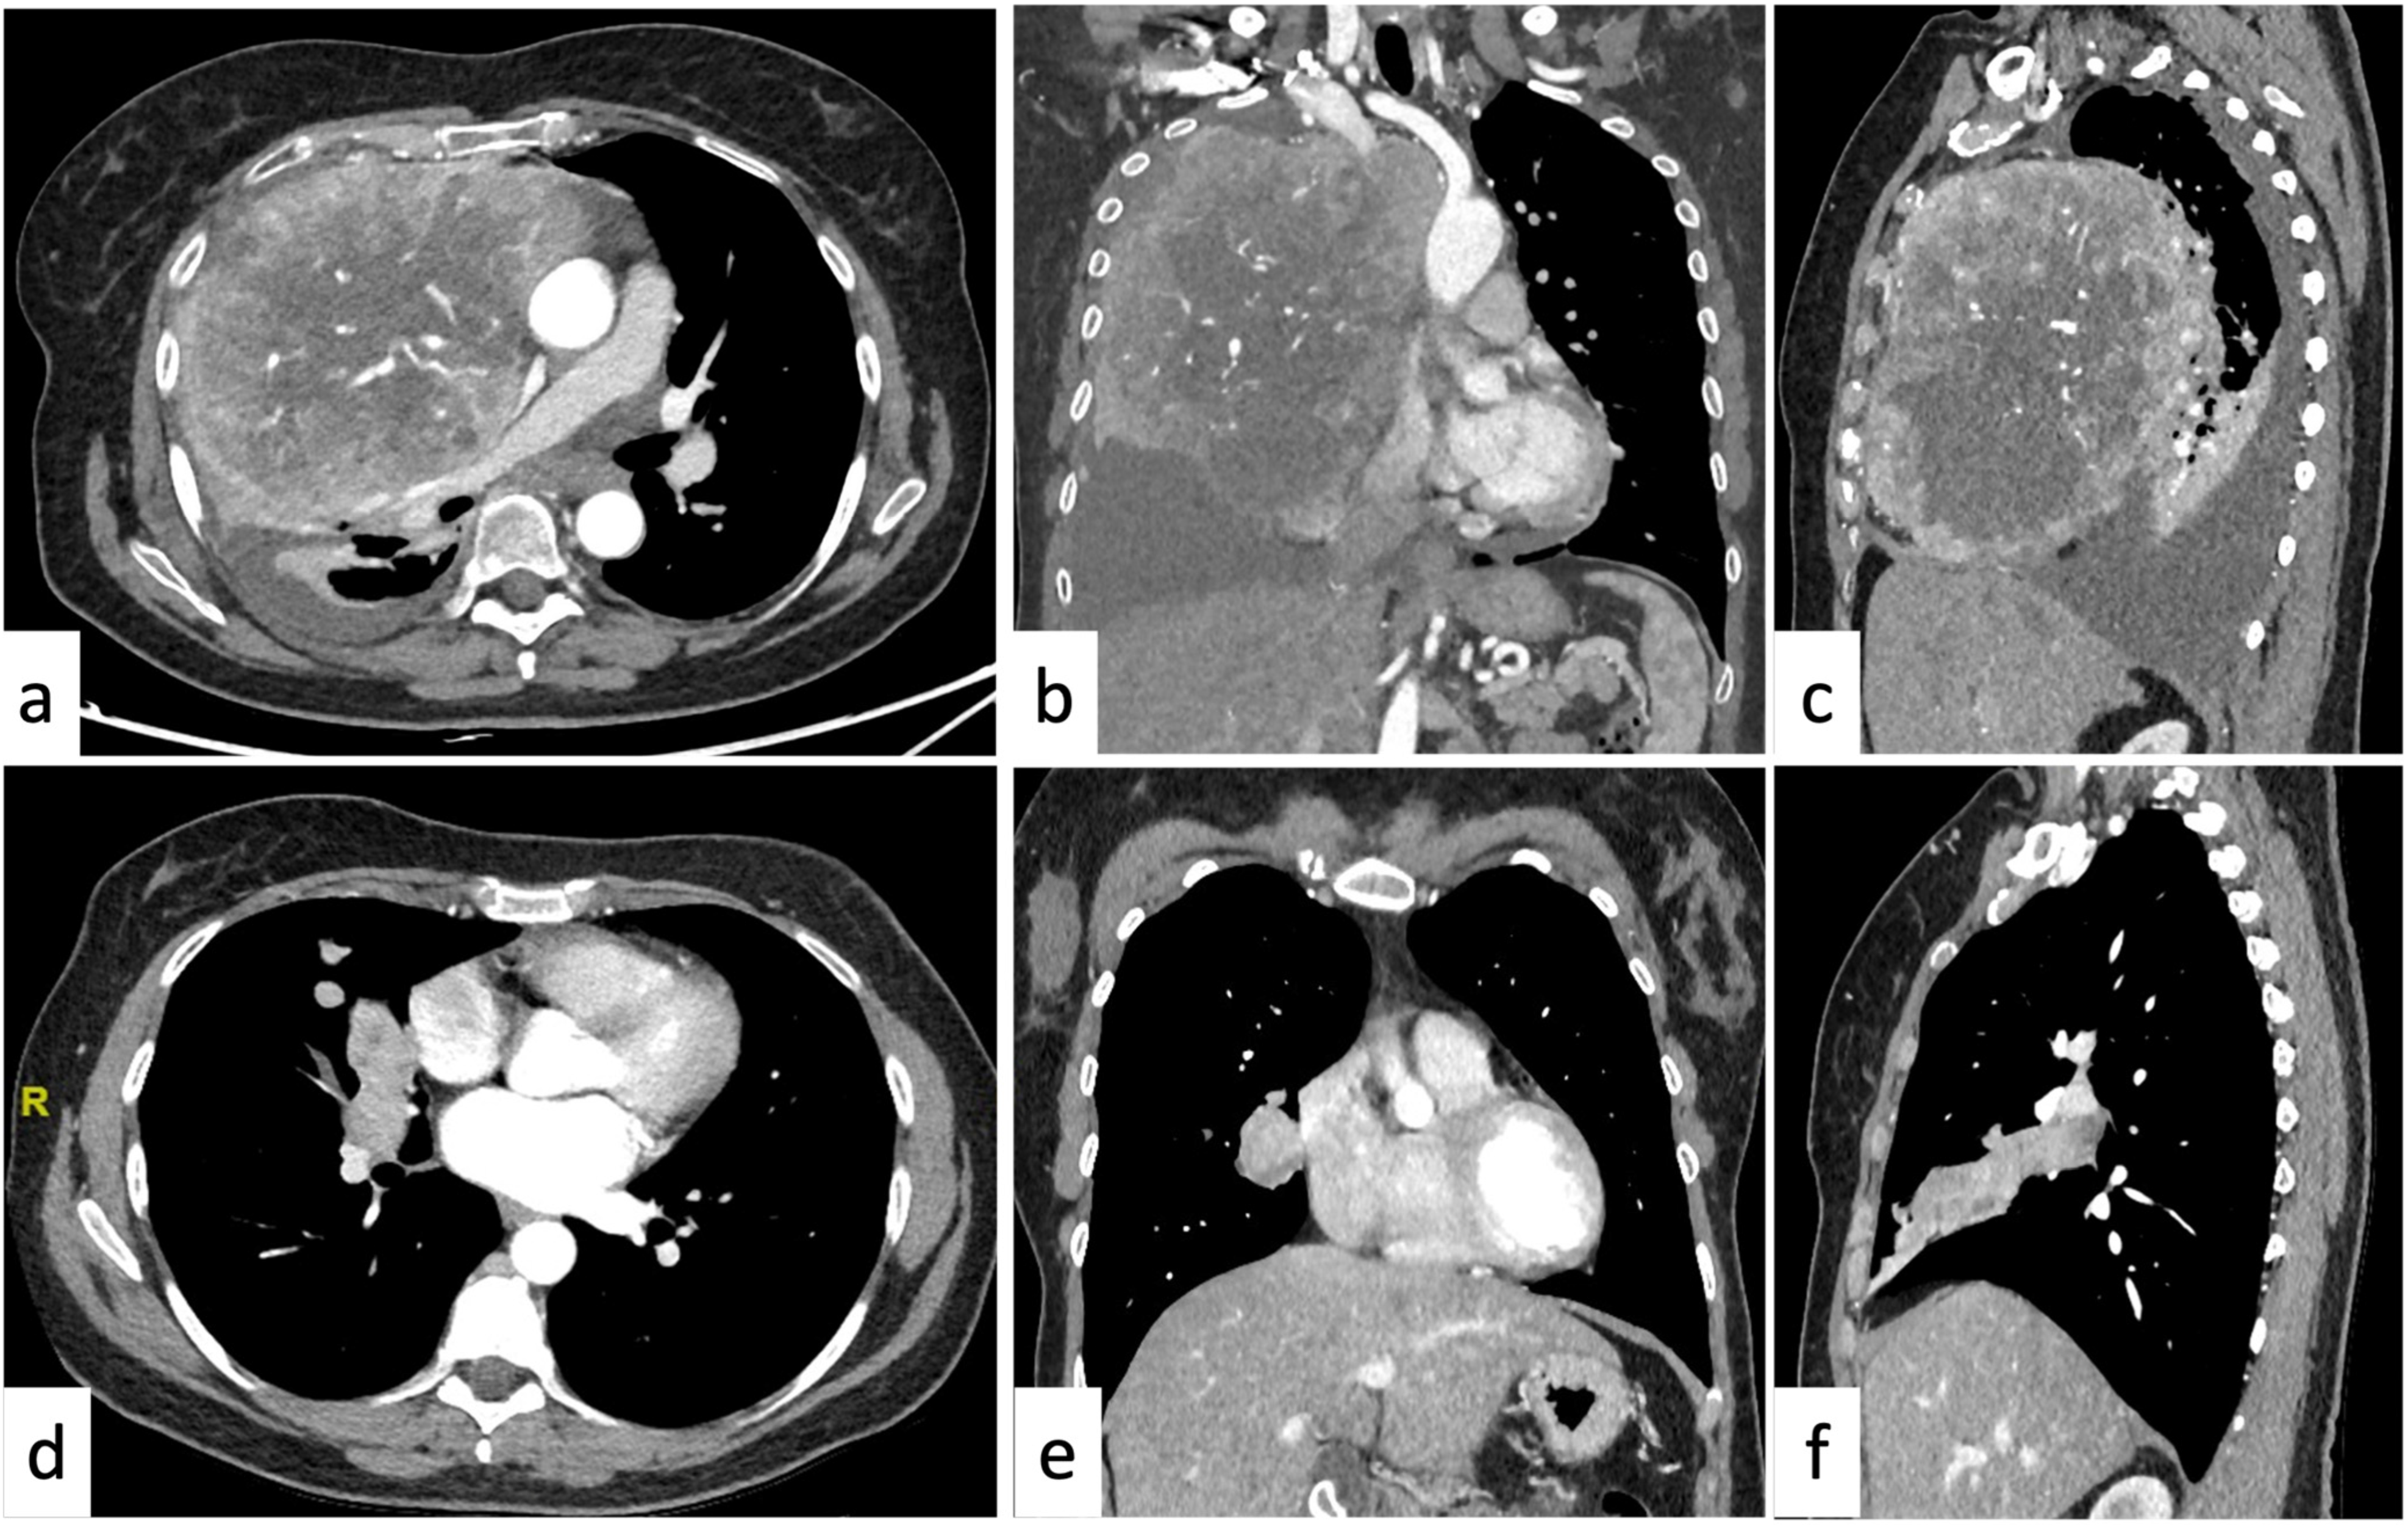

2.4. More than One Mediastinal Compartment

3.1. Pleural Neoplasms

3.2. Tumorlike Pleural Lesions